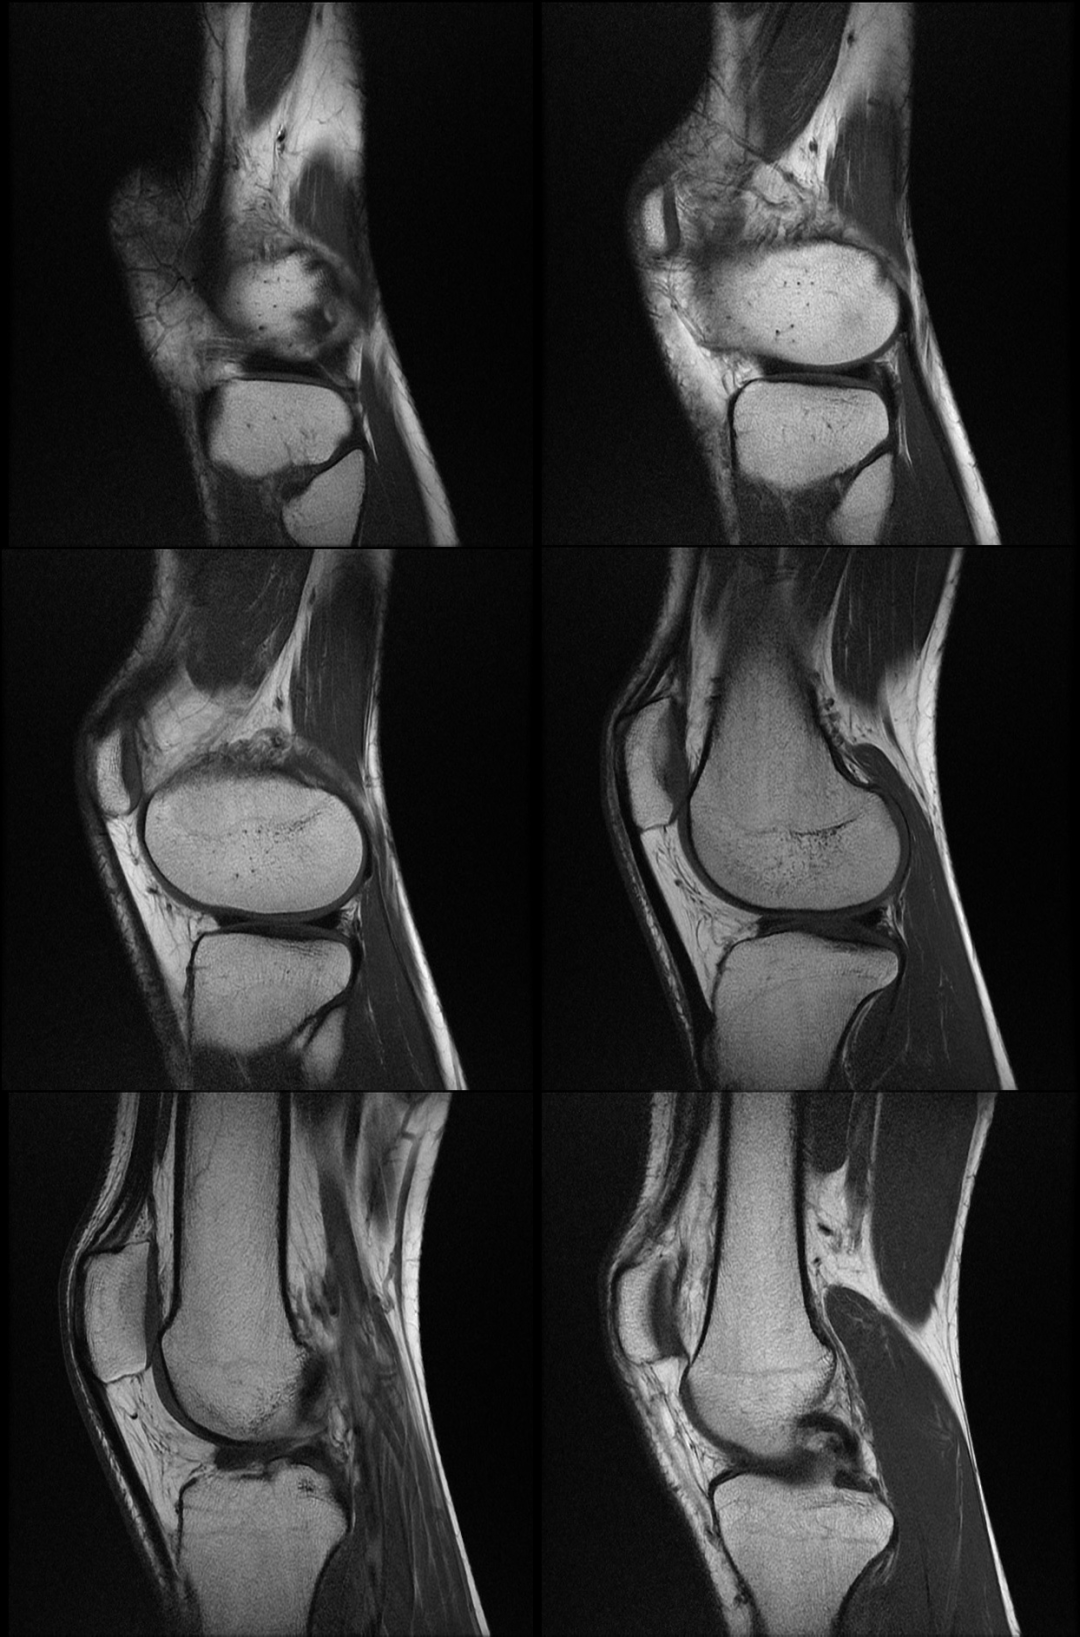

主诉:右膝关节外侧反复疼痛不适半年余,近一个星期疼痛加重。现病史:患者右膝关节外侧间歇性疼痛不适半年余,近一个星期疼痛加重,屈膝时明显,门诊行膝关节 X 线片检查,未见明显异常。患者否认手术史/外伤史。为进一步明确情况,我们建议患者行膝关节磁共振检查;图像如下:T1

T2 压脂

冠状位

大家是否发现什么异常?该患者是膝外侧疼痛不适的症状,我们重点观察了外侧半月板及外侧副韧带,但是我们发现是正常的;

但是我们发现有一个地方信号不对;

大家发现了没有?那这是什么呢?

那么我们刚刚看到信号增高的就是髂胫束,排除了半月板和外侧副韧带的问题,那么膝关节外侧疼痛是不是这个原因导致的呢?

1 T2WI PD 序列上可以显示靠近股骨外侧髁与髂胫束之间的信号增高,边界不清,外侧滑膜增厚;

2 髂胫束靠近股骨外侧髁水平出现增厚改变,部分严重患者可以出现连续性中断;3 髂胫束表面或深部信号明显增高;4 可伴股骨外侧髁反应性骨髓水肿